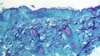

ကွန်ဂို သမ္မတ နိုင်ငံမှာ ၁၉၉၆- ၁၉၉၇ ခုနှစ်က မျောက်ကျောက်ရောဂါ ကူးစက်ရောဂါ ဖြစ်ပွားမှုမှာ မျောက်ကျောက်ရောဂါ လူနာ တဦးရဲ့ လက်မှာ ကူးစက် ဖြစ်ပွားနေပုံ။ ဓာတ်ပုံ - CDC/Brian W.J. Mahy/Handout via REUTERS